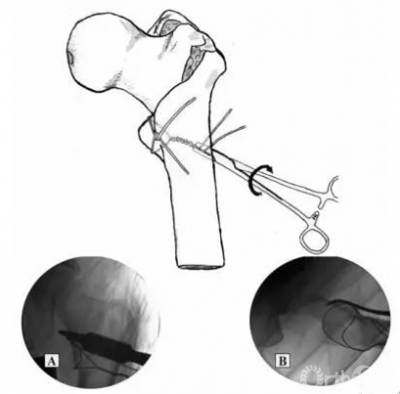

Fig.3.Minimally invasive applicationg of cerclage wires(Cerclage Passer.Synthes,Oberdorf,Switzerland).(A)Dividable forcep-clamped(B)Dividable forcep-opened.